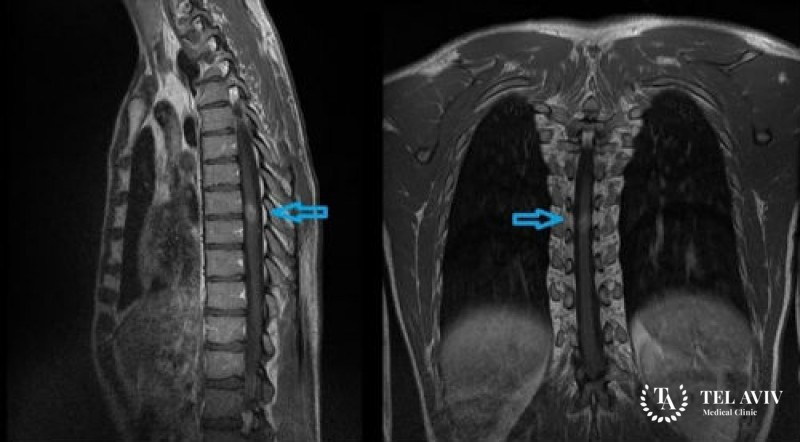

- МРТ покажет распространение опухоли, ее границы, характер и структуру. Является наиболее информативным способом, благодаря четкой визуализации.